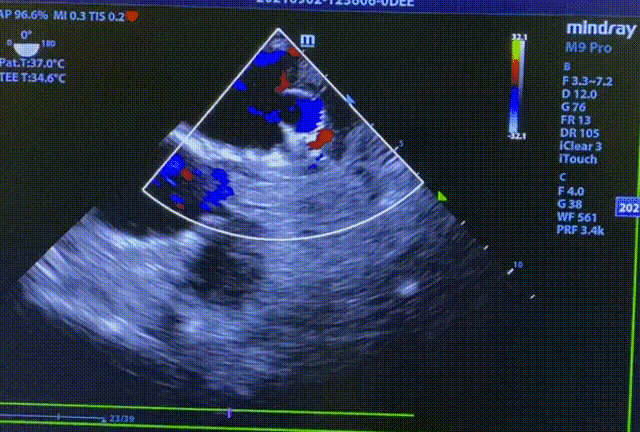

常规肝位造影显示,左心耳锚定区约26mm, 开口约29mm, 因此选择型号为LT-LAA-2834的LAmbre™左心耳封堵器对患者实施封堵。LAmbre™植入过程一步到位,U型钩均完全展开。随后复查造影及TEE结果,封堵盘呈“碗状”形态完美贴合于左心耳口部,无残余分流,牵拉测试稳定,综合评估符合COST原则,随后完美释放,封堵效果理想。术后,患者各项指标正常,身体恢复良好。

封堵器牵拉测试稳定

释放后TEE检查(135°)